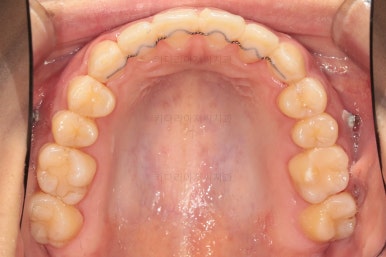

부산치아교정치과 초진 시 입안의 모습입니다.

앞니쪽이 위아래 모두 삐뚠 상태였고요.

왼쪽은 덧니로 툭 튀어나가 있고, 상대적으로 작은 앞니는 안으로 말려 들어가 아랫니와도 거꾸로 물리는 상태였습니다.

어금니도 물론 약간 삐뚤긴 하지만 앞니만큼 심한 상태는 아니었고 맞물리는 기능도 큰 불편함은 없으신 상태였습니다.